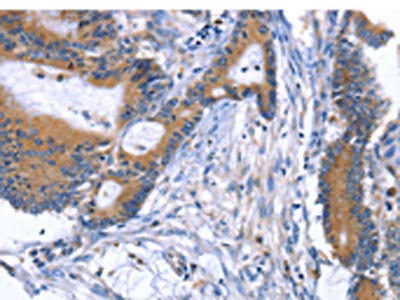

The image on the left is immunohistochemistry of paraffin-embedded Human cervical cancer tissue using CSB-PA830451(ARRB1 Antibody) at dilution 1/50, on the right is treated with fusion protein. (Original magnification: ×200)

The image on the left is immunohistochemistry of paraffin-embedded Human colon cancer tissue using CSB-PA830451(ARRB1 Antibody) at dilution 1/50, on the right is treated with fusion protein. (Original magnification: ×200)